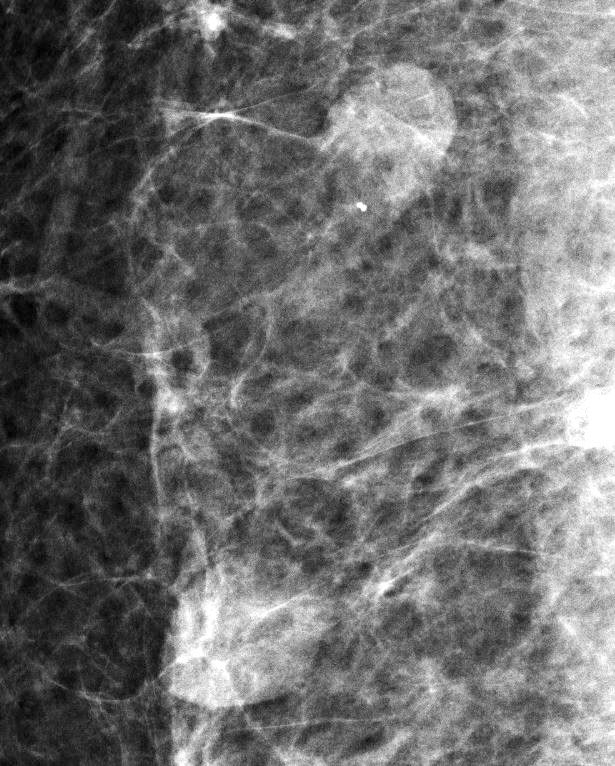

- Well circumscribed, homogenous, hyperdense or isodense, solid mass (Clin Imaging 2018;51:300)

- Typically devoid of calcifications

- Hypoechoic on ultrasound, may have posterior enhancement

- May be multilobulated

- Bilateral and multicentric tumors rare (Mod Pathol 1996;9:786, Int J Surg Pathol 2018;26:242)

Radiology images